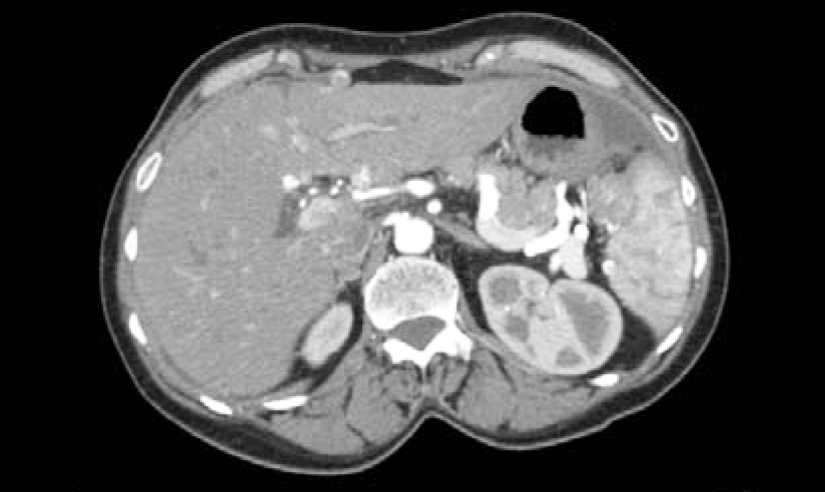

A 55-year-old female with no significant PMH and who had been postmenopausal for five years, presented with the complaint of abdominal pain, bloating, nausea and vomiting that initially occurred three months before admission. Her symptoms started with indigestion, then progressed to nausea, vomiting, bloating and abdominal pain. She presented to an outside hospital, where an obstruction series noted several air fluid levels and haziness suspicious for ascites. A CT abdomen pelvis revealed large ascites, 11x8.7 cm heterogeneous mass displacing the uterus anteriorly and a 7x5.5cm heterogeneous mass in the right adnexa and omental nodularity (Figure 1, 2, and 3). The patient was then referred to a gynecologic oncologist due to suspicion for a gynecologic malignancy and sent to our ER for ongoing abdominal pain, nausea, vomiting and bloating.

Figure 1: CT scan abdomen and pelvis. Splenic implant present.

Figure 2: CT scan abdomen and pelvis. Large ovarian mass.

Figure 3: CT scan abdomen and pelvis. 11 x 8.7cm heterogeneous mass displacing the uterus anteriorly.